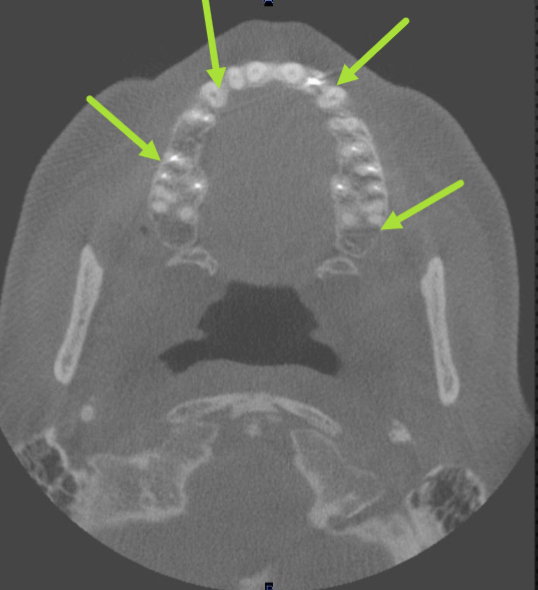

beeam hardening (braces)

what is the cause of this artifact